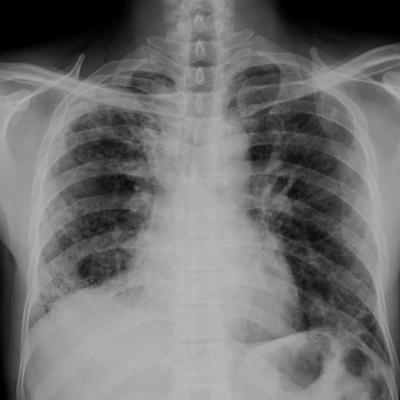

- Рентгенография. Рентгенологическими признаками интерстициальной пневмонии могут являться симметричные полупрозрачные затемнения по типу «матового стекла», в основном в нижних отделах легких; утолщение междолькового и внутридолькового интерстиция; кистозно-фиброзные изменения, периваскулярная и перибронхиальная инфильтрация и тракционные бронхоэктазы.

- Рентгенографическое и рентгеноскопическое исследования органов грудной клетки – обнаружение утолщенных соединительнотканных перегородок между долями и внутри них, симметричных полупрозрачных затемнений по типу «матового стекла», кистозно-фиброзных изменений, периваскулярной и перибронхиальной инфильтрации.